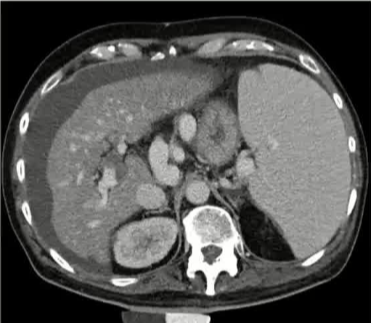

栓塞材料的可及性(例如病灶栓塞材料的可到达性)accessability (e.g. reachability of the nidus) 栓塞的预期深度intended deepness of embolization 如果需要让栓塞填满最后1mm 预期效果(例如:门静脉栓塞的炎症)intended effect (e.g. inflammation in PVE) 凝血状态(达到止血效果所需的时间)coagulation state (duration until hemostasis) 并发症(过敏、心律不齐、肺动脉高压、肝纤维化等)comorbidities (allergies, arrythmia, pulmonary hypertension, lung fibrosis etc.) 处于危险中的结构(包括下游部分-downstream和反流部分) structures at risk (downstream & backwash) 靶病变定位(浅层与深层) target lesion localization (superficial vs. deep) 不会选择一些会引起炎症的东西,因为那会病人来说真的很痛苦浅层病变 栓塞所需的速度(例如:危及生命的出血情况)required speed of embolization (e.g. life threatening hemorraghe) 院外专业人员(DSA技术人员和介入放射科医生)local expertise (technicians & IR's) 可用性与定价 availabilty & pricing Patient assessment for the choice of the ideal liquid emboli 影像学 62岁 男性

腹腔侧支循环

腹水 水肿 jaundice 男性乳腺发育症 多血管蜘蛛状结构(提示存在食管静脉曲张) 肝掌 (palmar erythema) 指表皮或真皮层受刺激后毛细血管扩张引发的局部皮肤发红现象 和患者说话